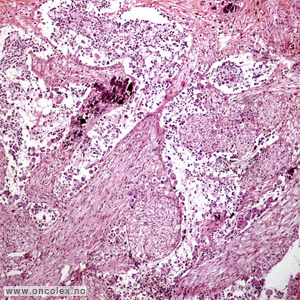

Ondartet leversvulst

Hepatoblastom er her den hyppigste ondartete svulsten og består av umodent levervev. Hos litt eldre barn kan også hepatocellulært karsinom ses.